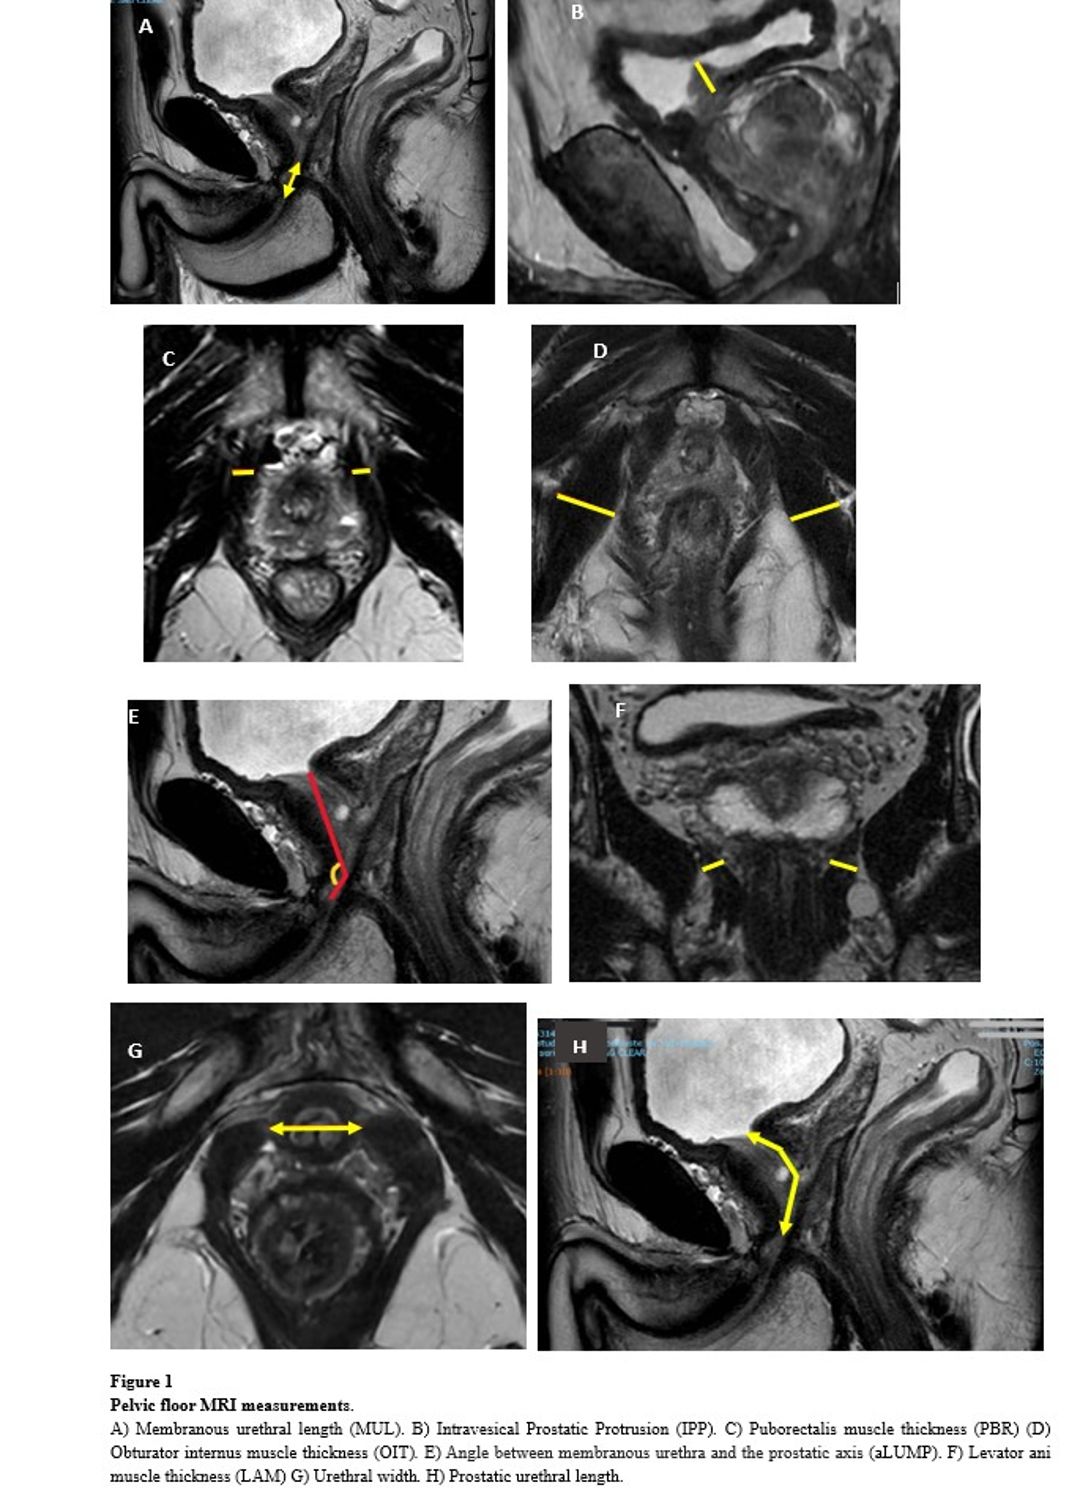

Prospective analysis of 57 patients undergoing RALP. All patients were advised to perform pelvic floor exercises. The MRI measurements studied included membranous urethral lenght, levator ani muscle thickness, prostatic urethral length, obturator internus muscle thickness, puborectalis muscle thickness, intravesical prostatic protrusion, urethral width, prostate volume, angle between membranous urethra and prostate axis and ratio levator ani/prostate volume (figure 1).

Figure 1 Preoperative MRI measurements